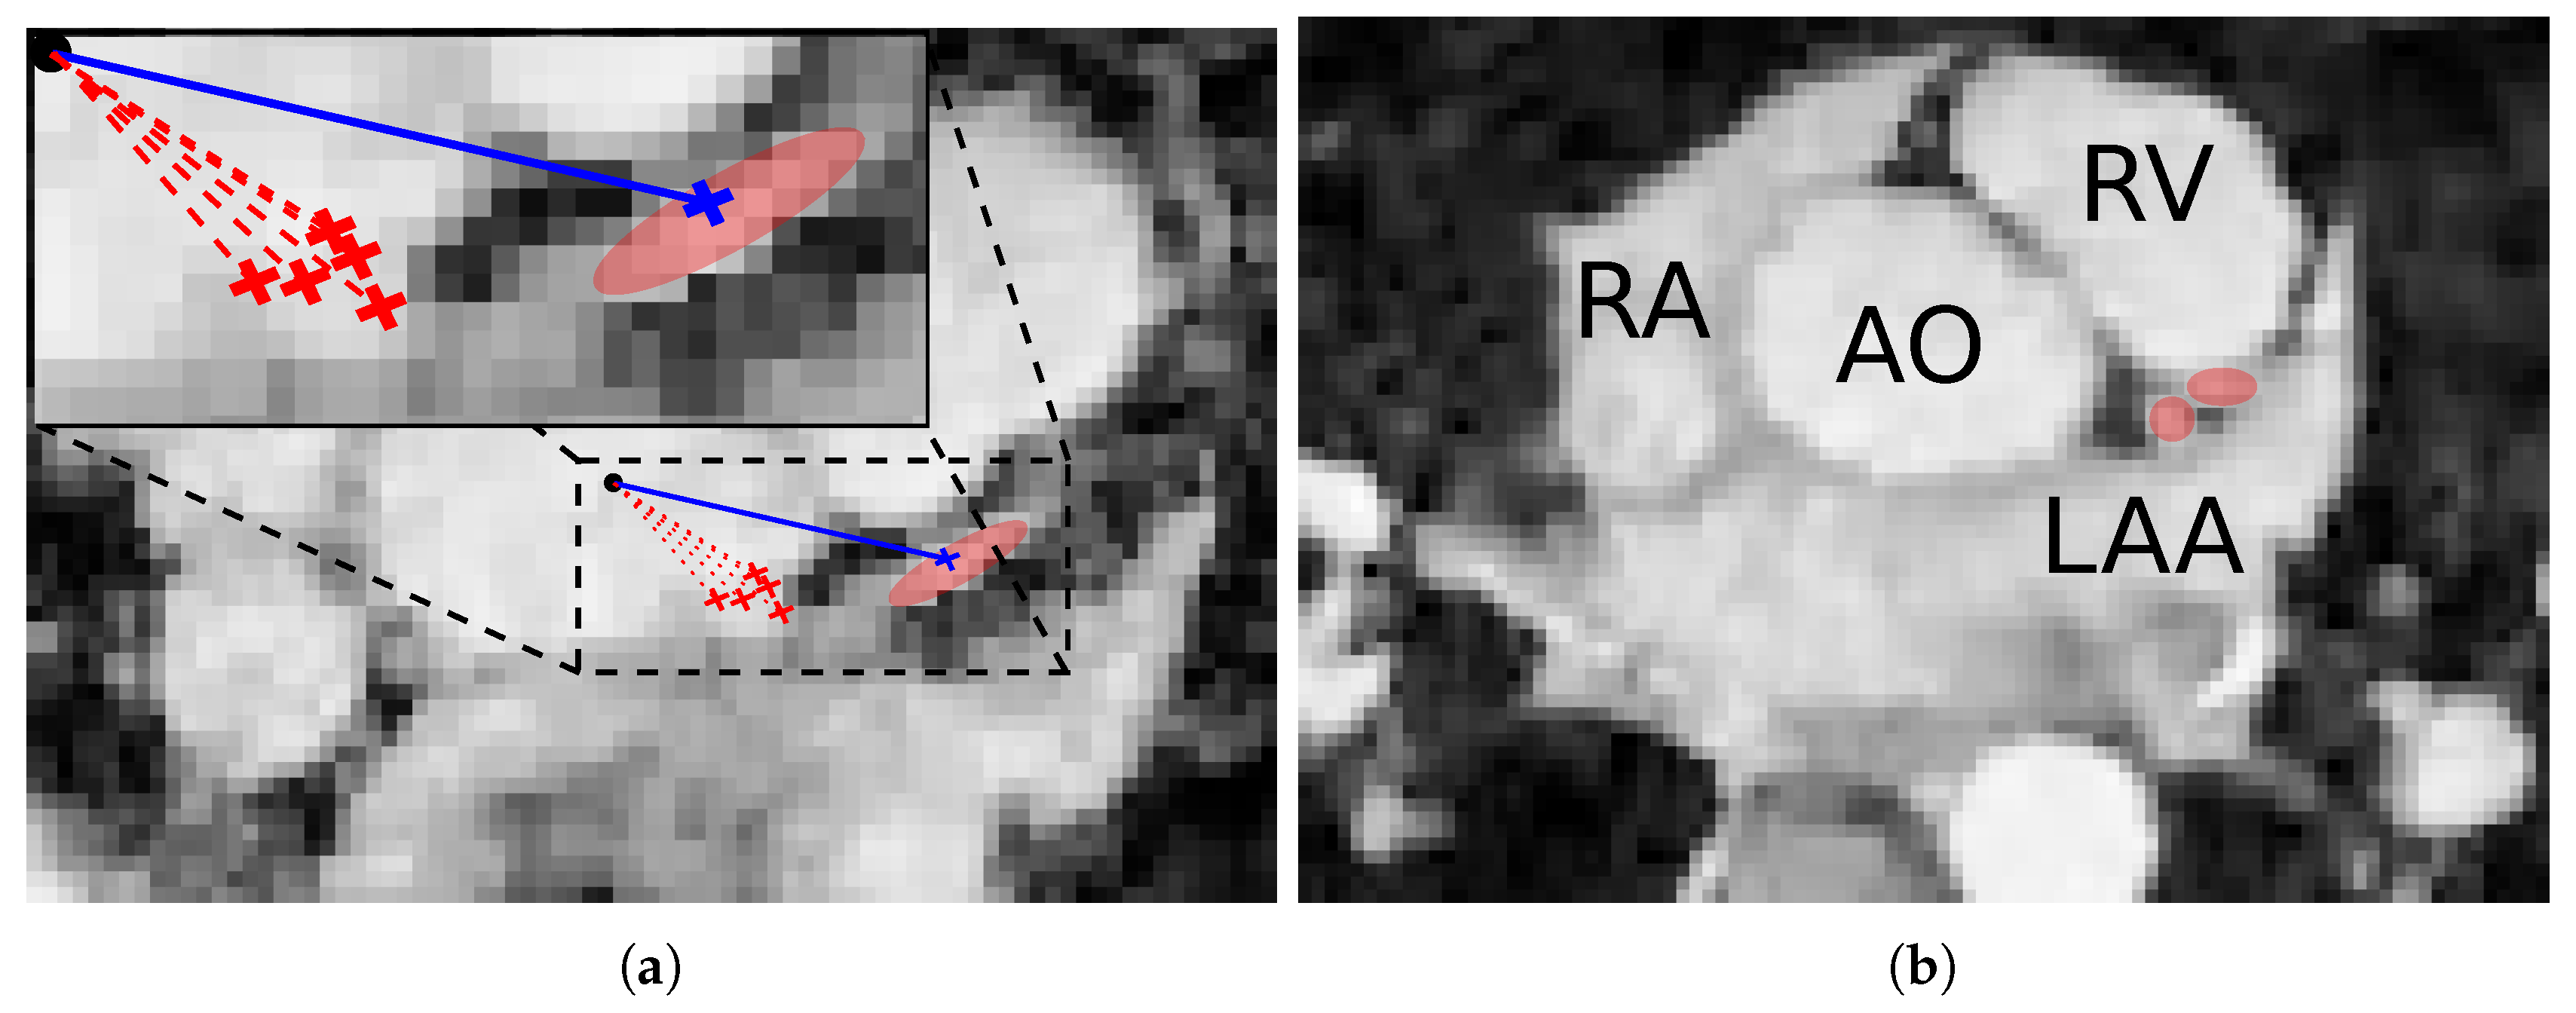

3.5. Ostia Detection

3.6. Coronary Centerline Extraction